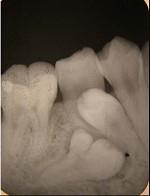

融合牙是 ( )A.仅见于乳牙B.仅见于恒牙C.两牙牙釉质相连D.两牙牙本质相连E.两牙牙骨质相连

问题 融合牙是 ( )

选项 A.仅见于乳牙 B.仅见于恒牙 C.两牙牙釉质相连 D.两牙牙本质相连 E.两牙牙骨质相连

答案 D